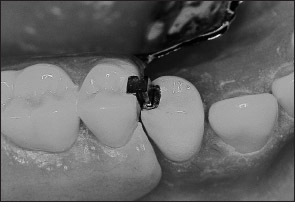

Unlike extracoronal retainers, intracoronal retainers are contained entirely within the contours of a clinical crown (Fig 1-4). Consequently, the use of intracoronal retainers generally requires the fabrication of two or more specially designed, complete-coverage crowns. In most instances, retention of intracoronal removable partial dentures is dependent upon exact parallelism of the retentive assemblies. Each assembly consists of two parts, commonly termed matrix (“female”) and patrix (“male”). Figure 1-5 illustrates the joining of a patrix and matrix to form a functional retentive unit. When a dislodging force is applied to the removable partial denture, binding occurs between the external walls of the patrix and the internal walls of the matrix. This binding results in retention of the prosthesis.

Fig 1-5 When joined, matrix and patrix components form a closely fitting retentive assembly.